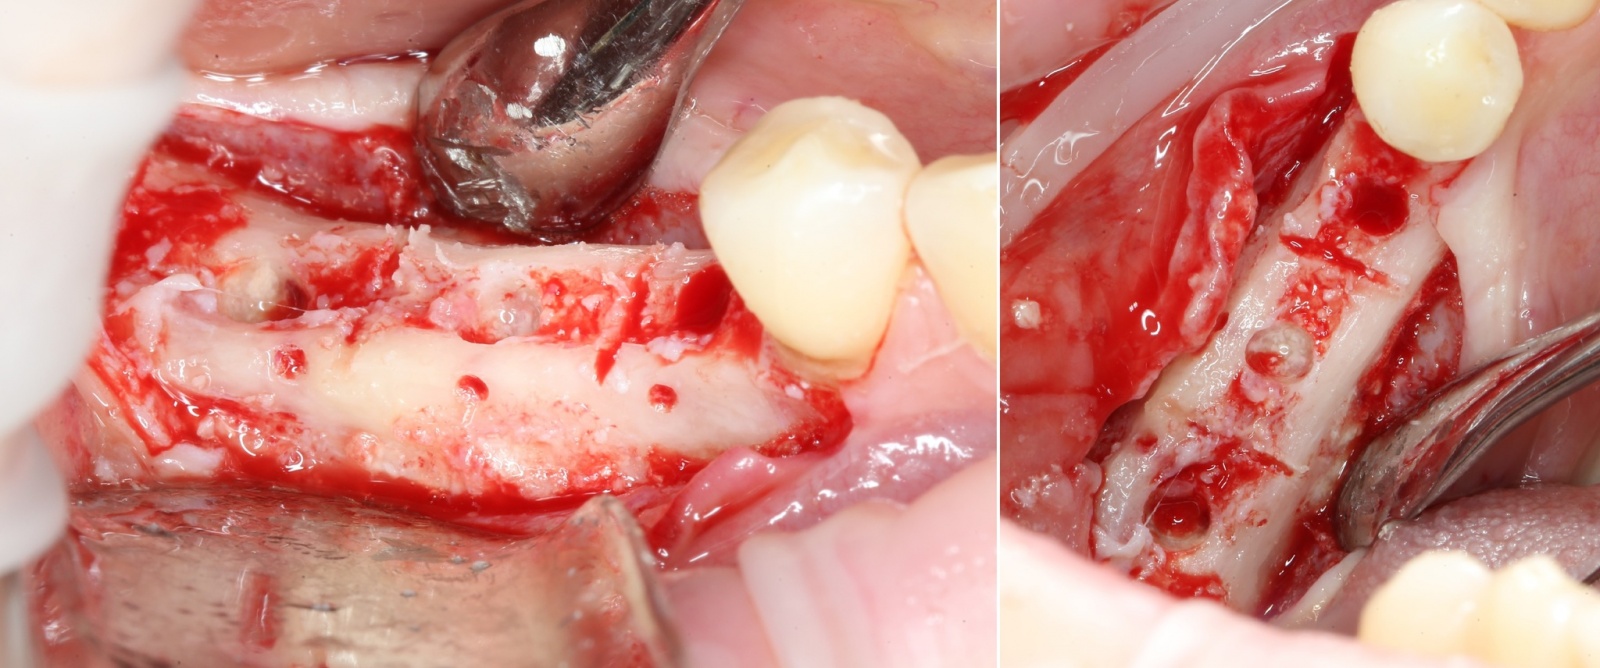

После того, как анестезия подействовала, при помощи скальпеля производится разрез, а с помощью распатора – скелетирование кости. (отделение надкостницы от компактного вещества кости).

Разрез:

Скелетирование:

Ультразвуковой наконечник располагается перпендикулярно кости, вследствие чего формируется «траншея» вдоль того участка, где отсутствуют зубы. Глубина этой траншеи составляет 10 мм.

При помощи специальных остеотомов

аккуратнейшим образом производится «расклинивание» костных фрагментов. Почему аккуратнейшим? А потому, что костную стенку можно выломать, и вся операция может пойти по бороде.

Кость расщепили: